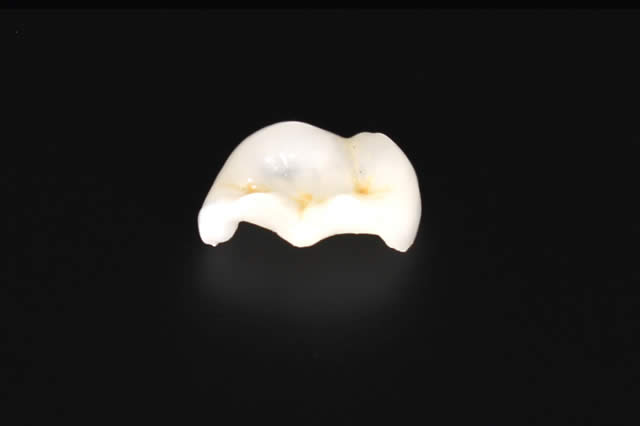

こちらでご紹介する治療は、全体的に噛み合わせの治療が必要な方に対し行う治療です。

審美治療は美しさだけではなく、歯の本来持った機能を引き出し、お体の健康を取り戻すことが本来の目的です。

パール歯科医院では、機能を伴っていない見た目だけの審美治療は行いません。どうぞ、安心してご相談にお越しください。

ワックスで模型を作り、歯の正確な位置や噛み合わせ等を診断します。

その上で、仮歯を作製していきます。

仮歯を作製して実際に付けて頂き、噛み合わせや見た目などの確認を行います。

仮歯を付けた時に見つかった細かい修正箇所を作製時に反映させ、人工歯を作っていきます。

完成した人工歯を取り付けます。

患者さまのご希望通りの“自然で白い歯”の治療が完了しました。

この後、口腔内の健康維持のため、定期健診(クリーニング)にお越しください。